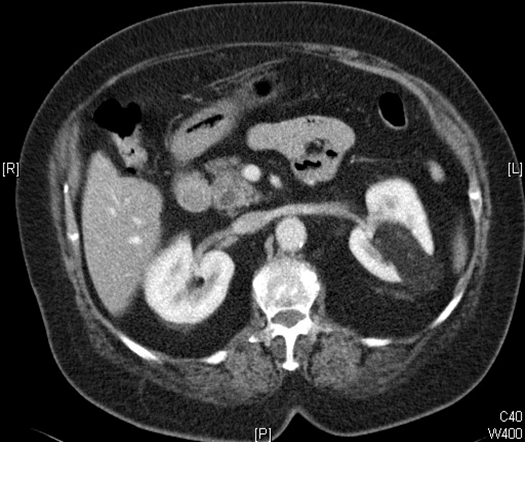

What does the CT image show? How is this treated?

Angiomyolipoma. Embolization